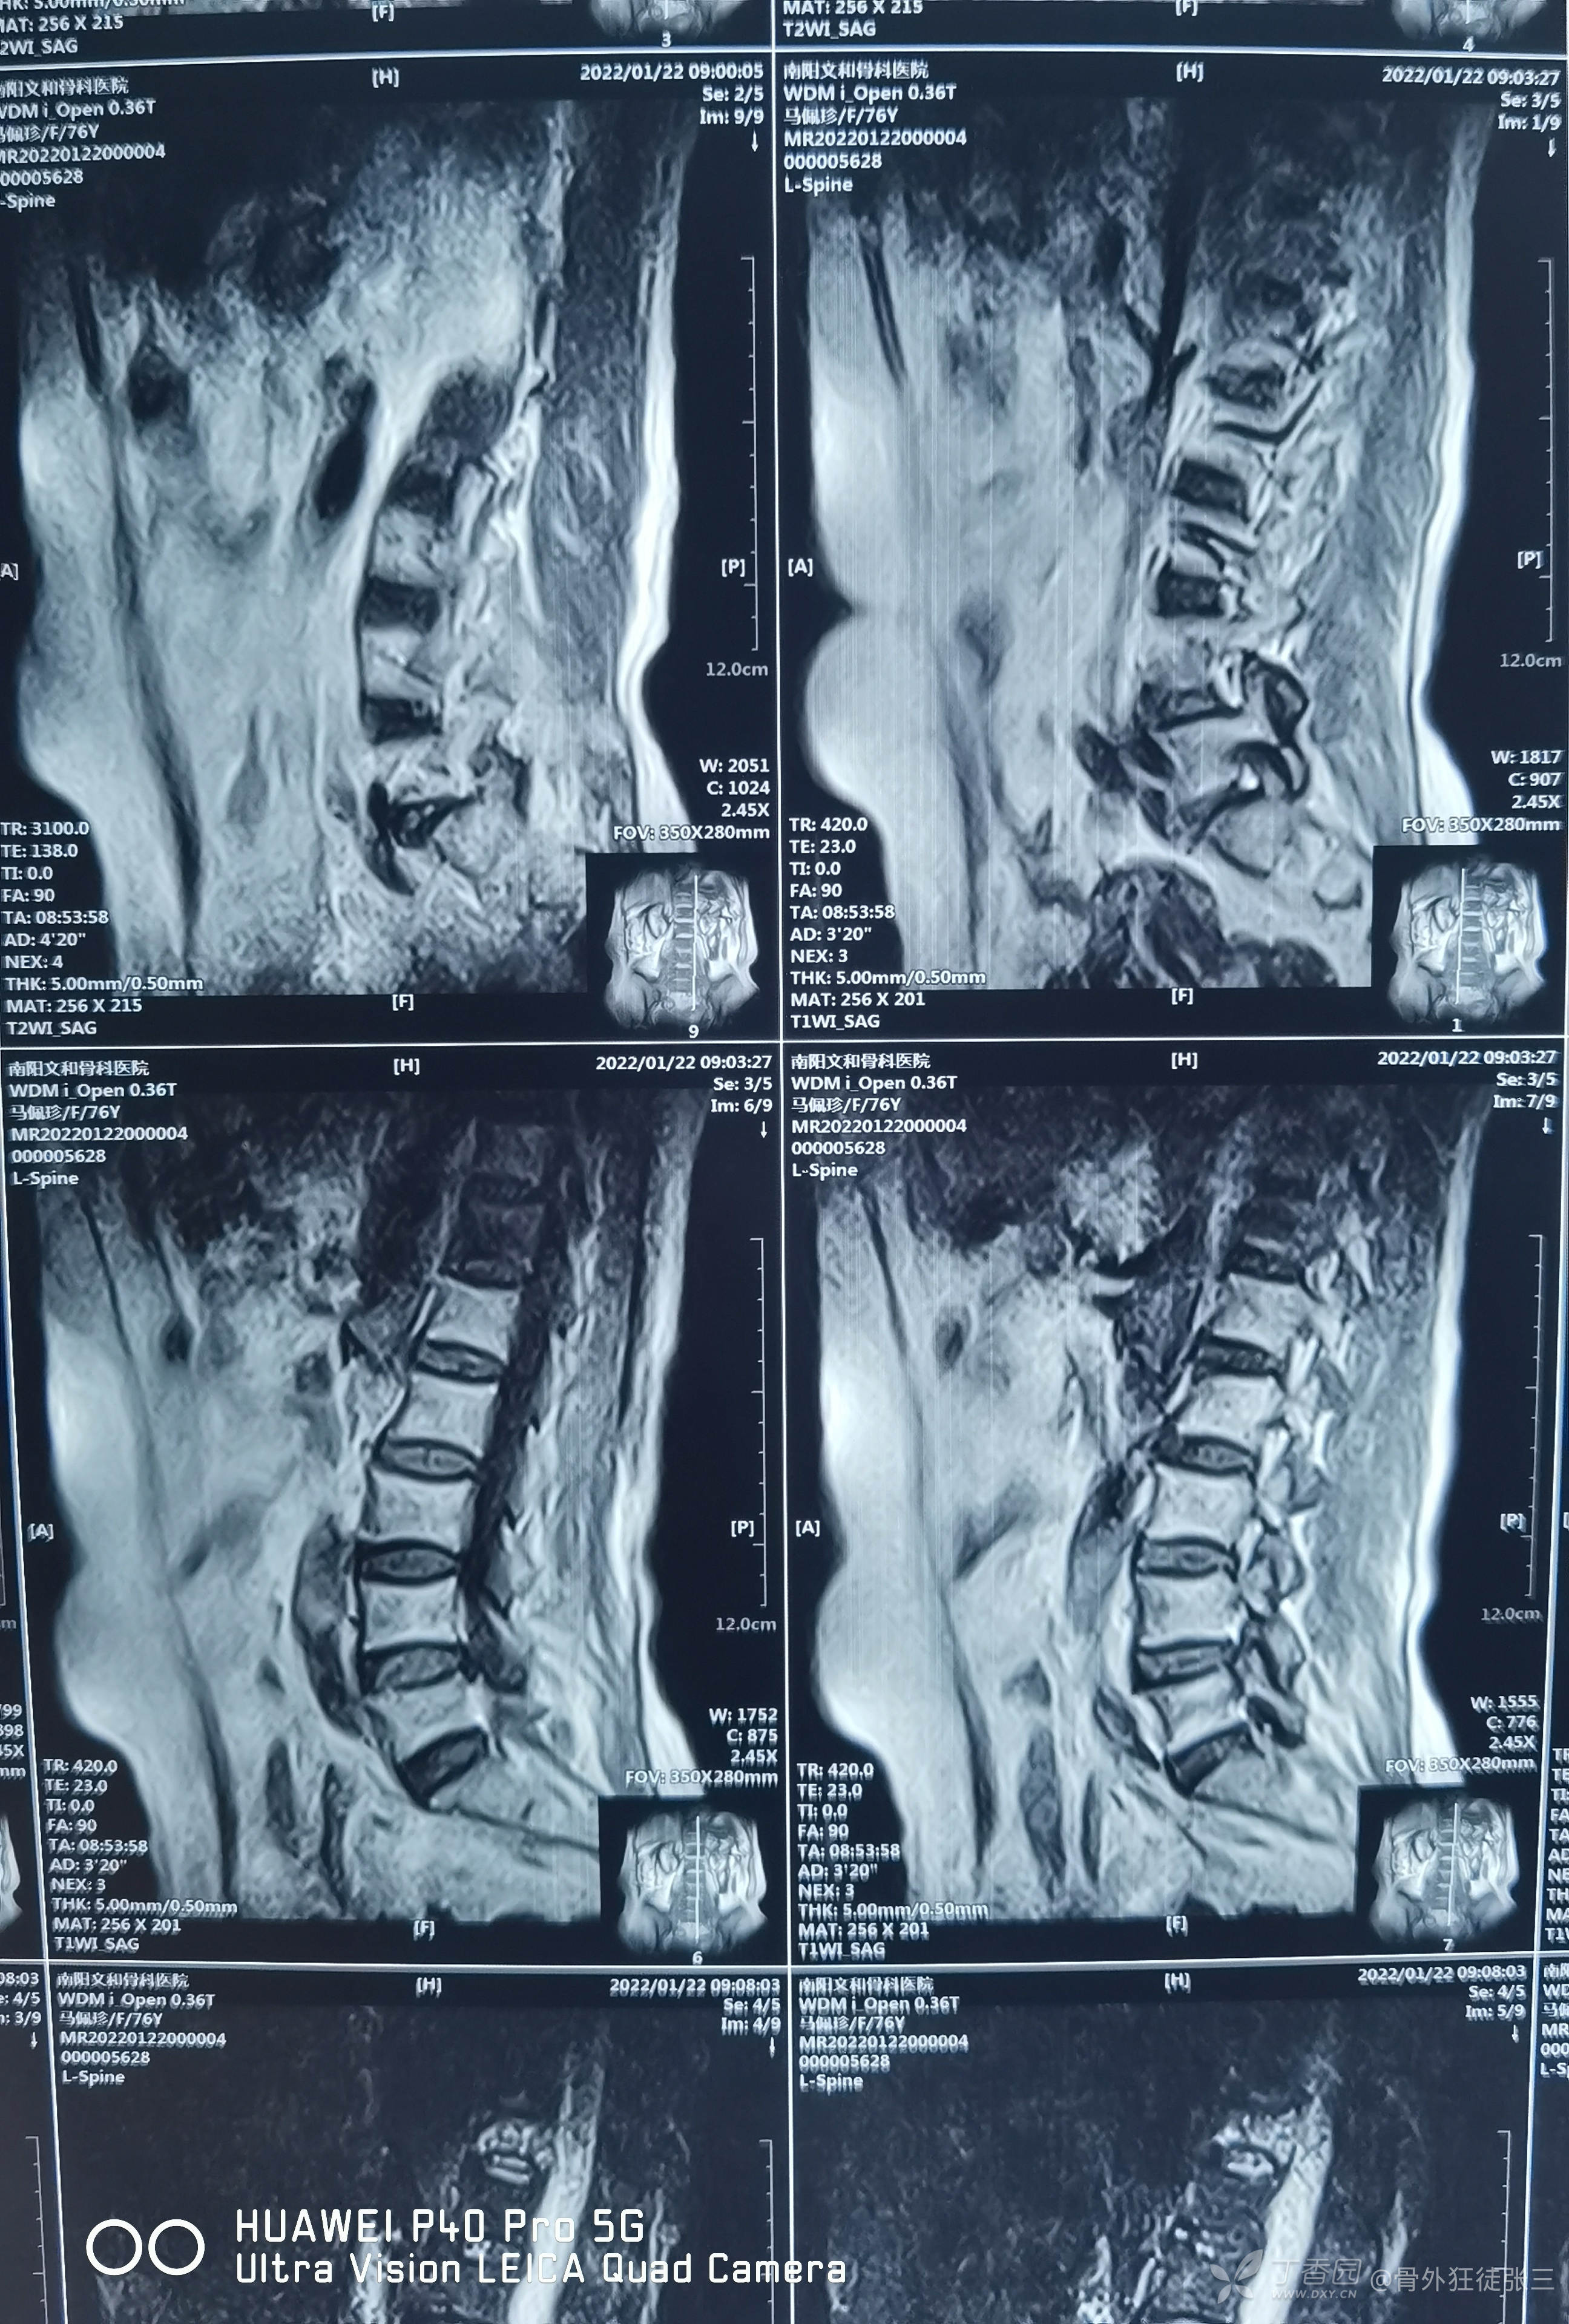

脆性骨折:胸12椎体压缩骨折椎体成形术1例

患者:女性

年龄:76岁

主诉:跌倒摔伤腰部致疼痛、活动受限9小时。

辅助检查X线,CT,核磁示:

胸12椎体压缩骨折

骨密度检测示:骨质疏松